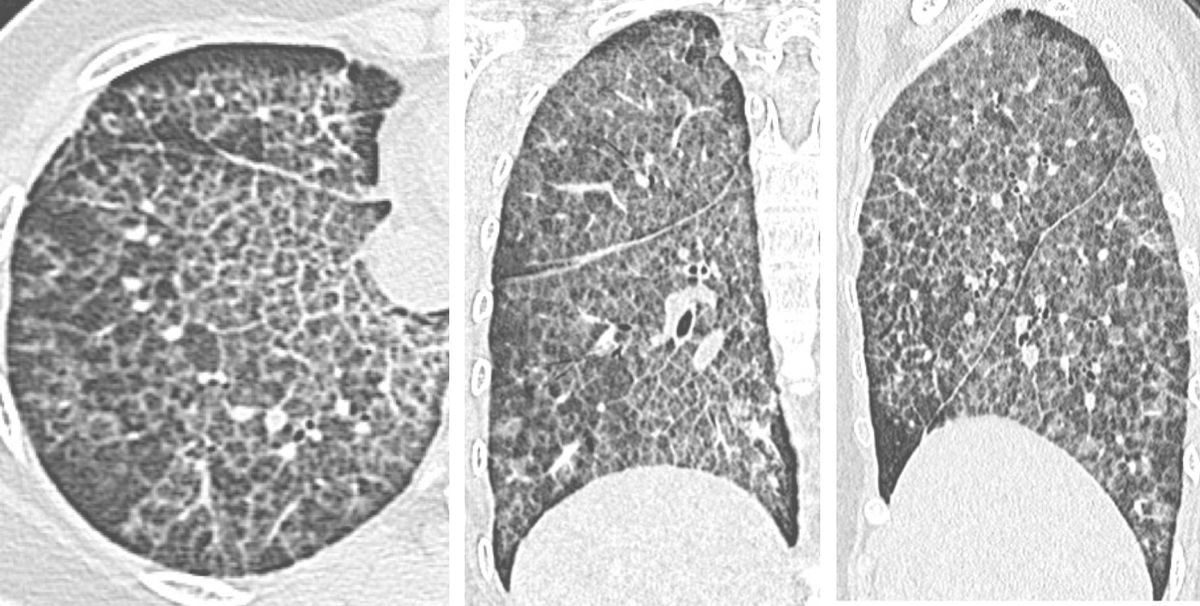

The diffuse crazy-paving pattern is quite distinctive in its classic, typical form.

48-yrs old in 2020 with diffuse lung disease and superimposed TB. Known to have ILD since 2014.

The CT scans consistently have shown a crazy-paving pattern, which now would be called an alveolar filling pattern as per the new guidelines.